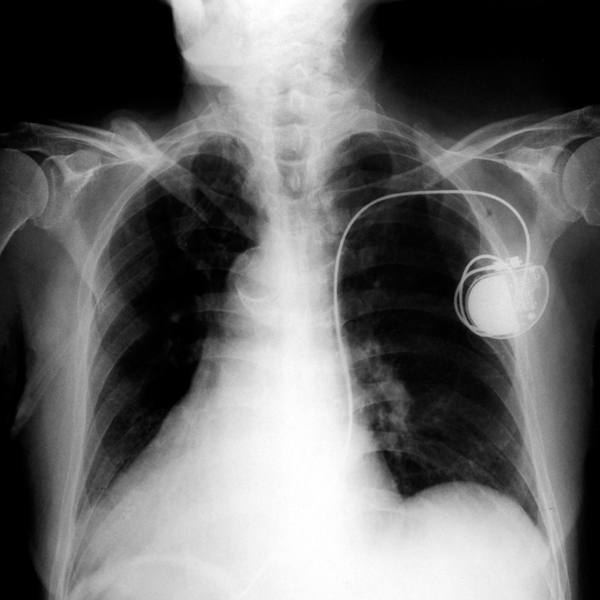

Can A Pacemaker Help A Fast Heartbeat . They may also operate as implantable cardioverter defibrillators, designed to shock the heart. A pacemaker helps the heart keep a steady beat. Your heartbeat is sometimes normal. A pacemaker also can help your heart chambers beat in sync and improve blood flow if your heart isn't pumping enough blood. The goals of tachycardia treatment are to slow a rapid heartbeat and to prevent future episodes of a fast heart rate. Your heartbeat is too slow and often irregular. Some pacemakers, called biventricular pacemakers, can treat heart failure. Atrial fibrillation can make your heart beat with an unsteady rhythm. If another health condition is causing tachycardia, treating. In some cases, a pacemaker may be needed to. A pacemaker is a small device that sends electrical impulses to the heart muscle to keep a suitable heart rate and rhythm. A dual chamber pacemaker checks, or paces,. If you have afib and your heart is beating too slowly, you might. If the device finds a slow heartbeat, it sends electrical signals to correct the beat. Your doctor may recommend a pacemaker to make your heart beat more regularly if: